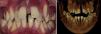

We present the case of a boy aged 12 years who presented with loose teeth that had erupted 6 years earlier. There was no history of trauma, infection or cancer involving the upper or lower jaw. The oral examination found an adequate mouth opening (Fig. 1), with small displacement of the teeth on palpation, and no signs of bone development, the teeth were simply covered by a reddened gum (Figure2 Fig. 2 ). The rest of the physical examination and the blood tests were normal. The 3D dental cone CT scan evinced the presence of osteolytic lesions in the mandible and absence of alveolar bone in the teeth of both the maxilla and the mandible, giving them the appearance of floating teeth (Figs. 2 and 3). The patient received a diagnosis of Gorham-Stout syndrome. It was managed with several bone grafts to correct the bone defects.